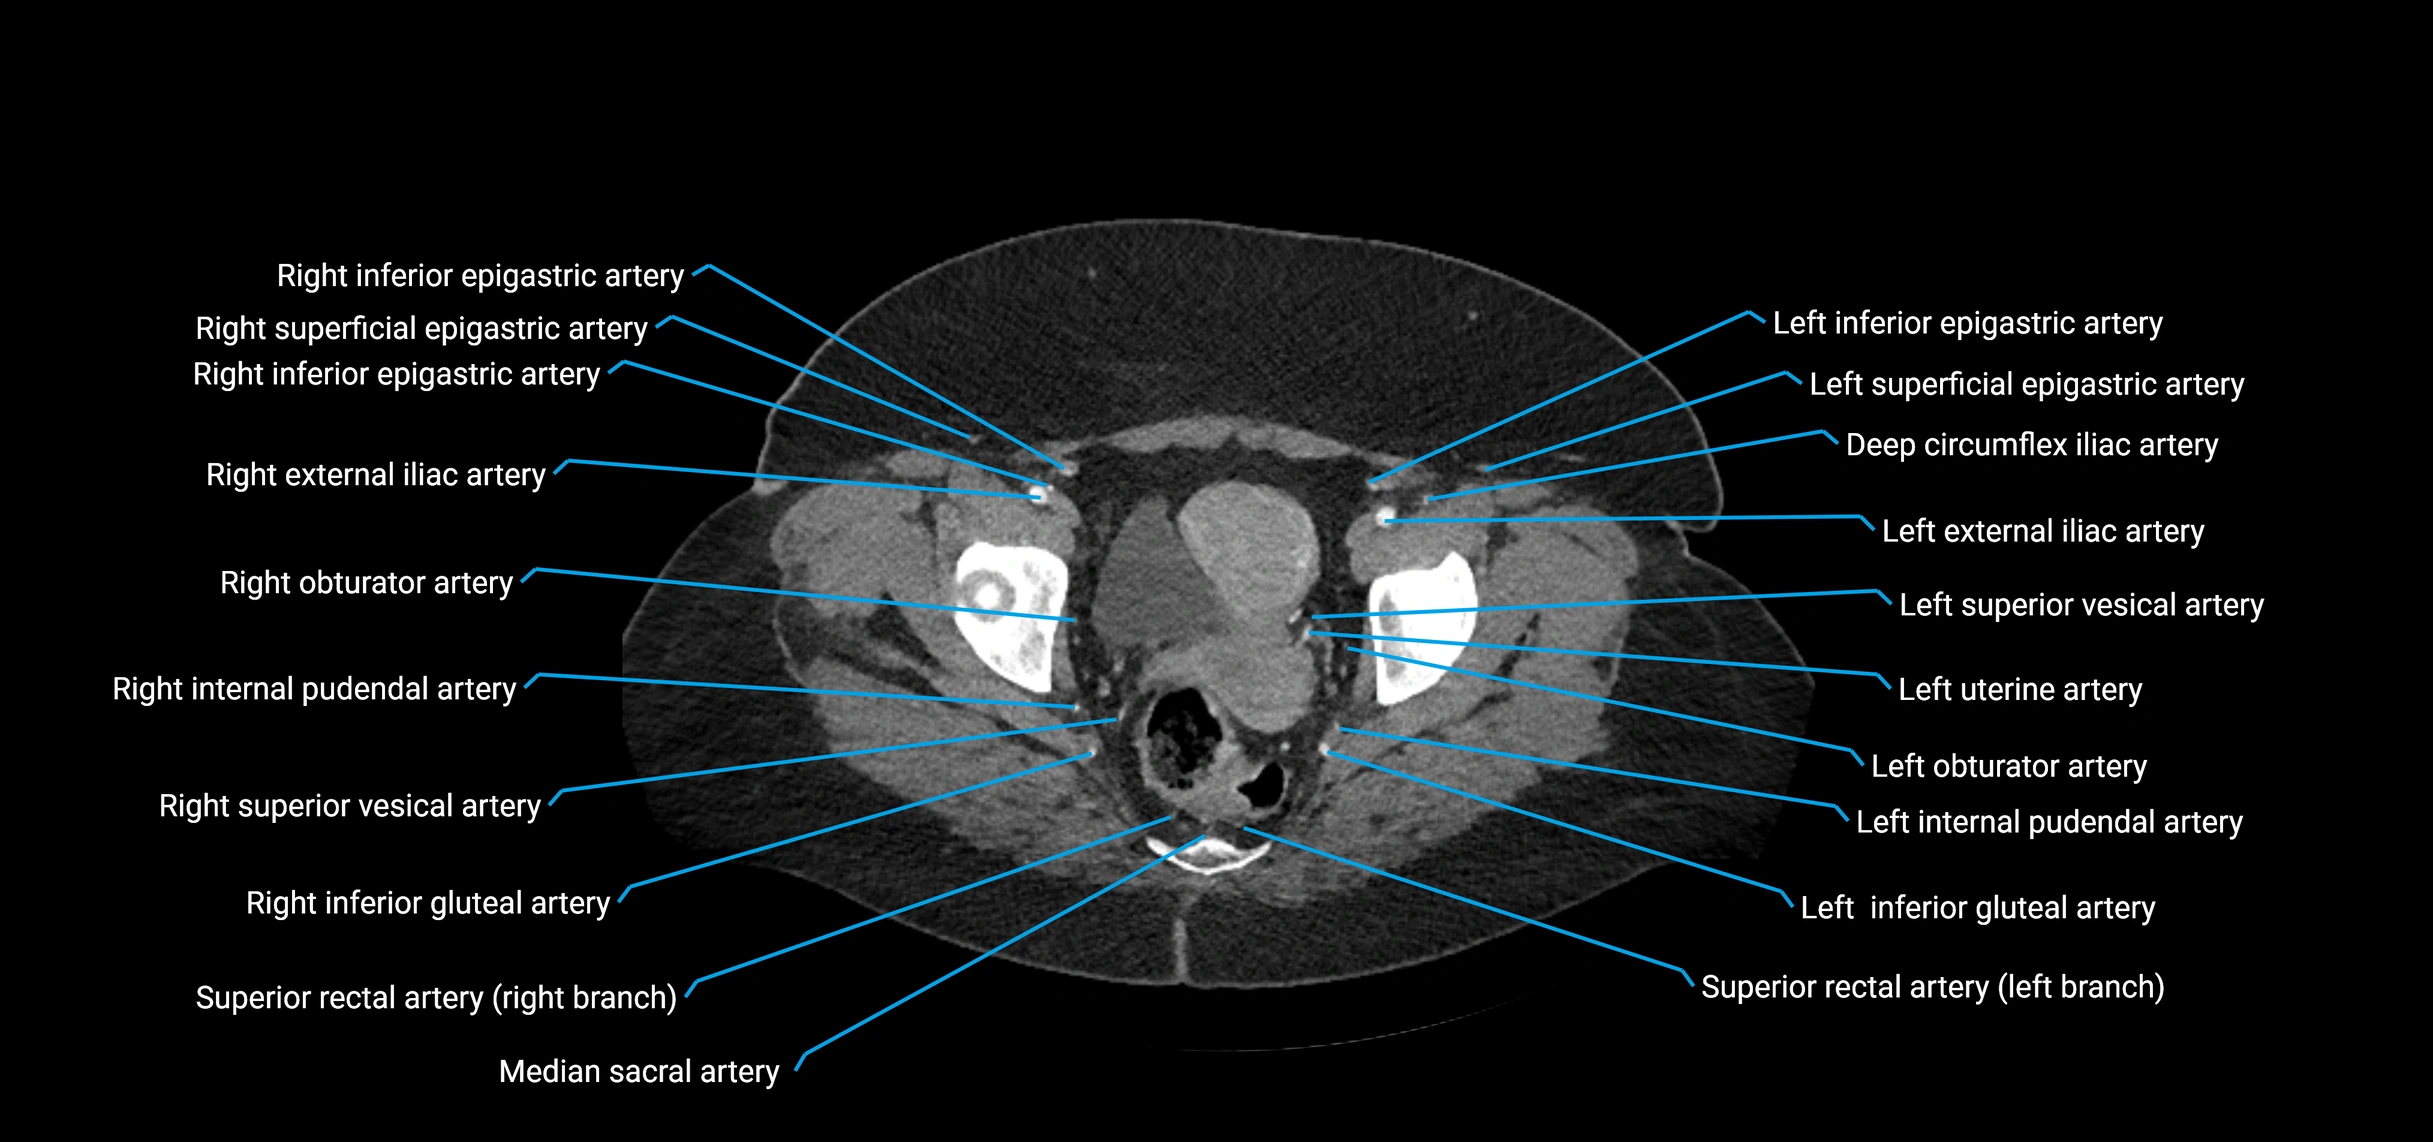

CT images

image

Contrast-enhanced CT (CTA):

• Gold standard for abdominal aortic imaging

• Provides excellent detail of lumen, wall, aneurysm, thrombus, and branch vessels

• Multiplanar and 3D reconstructions help in aneurysm measurement, stent graft planning, and dissection evaluation